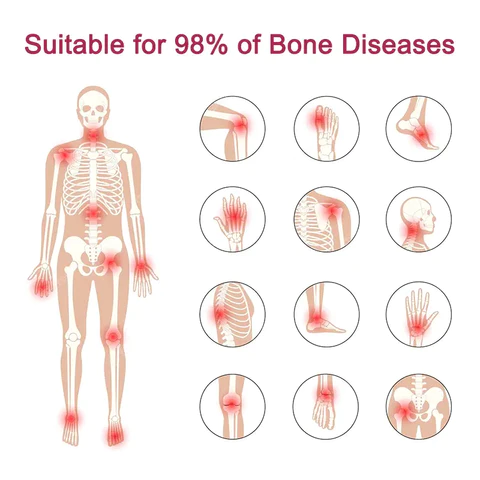

Using BBOJI™ Tigers Oil Spray can treat 98% of arthritis cases.

Include osteoarthritis, rheumatoid arthritis, bursitis, tendonitis, osteoporosis, gout, bunions deformities, ligament sprains and strains, and tennis elbow, etc.

- Improves various arthritis diseases, including osteoarthritis, rheumatoid arthritis, gout, psoriatic arthritis, fibromyalgia, lupus, etc.

- Suitable for hands, legs, knees, back, hips, feet, knuckles, and other affected body parts